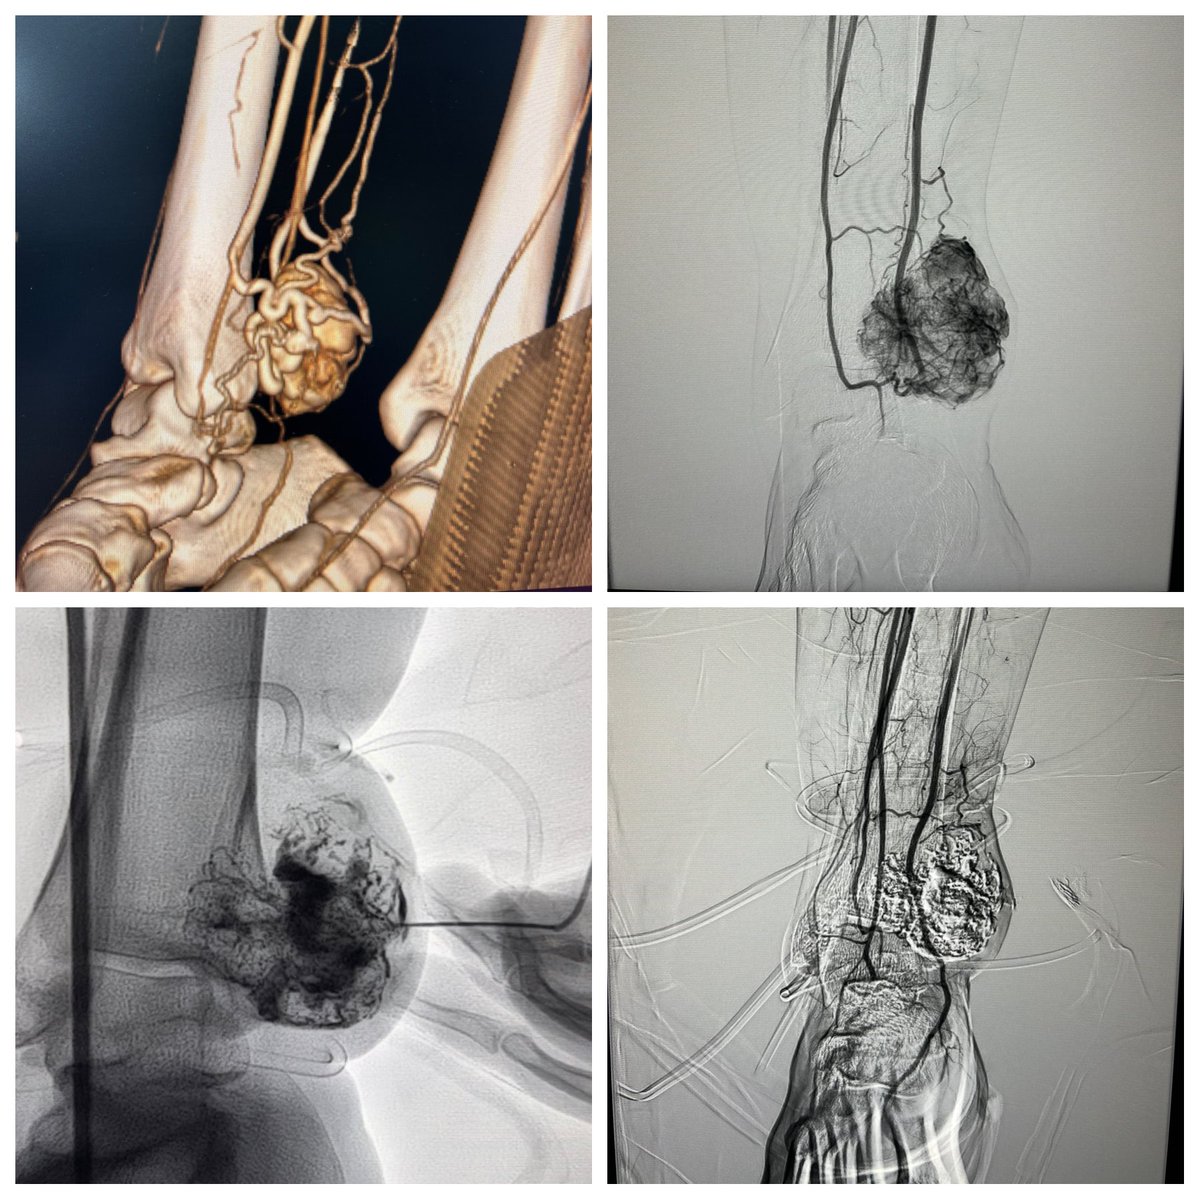

Cirrhotic patient with fundal varices and large PSS prior endoscopic flue injection now presented with massive upper GI bleed. Hb 6. Shunt occlusion with Double plugs - no further bleeds # Pinhole treatment for upper GI bleed @ISVIRIndia @No_cut_surgery @keithppereira @SRajesh_IR